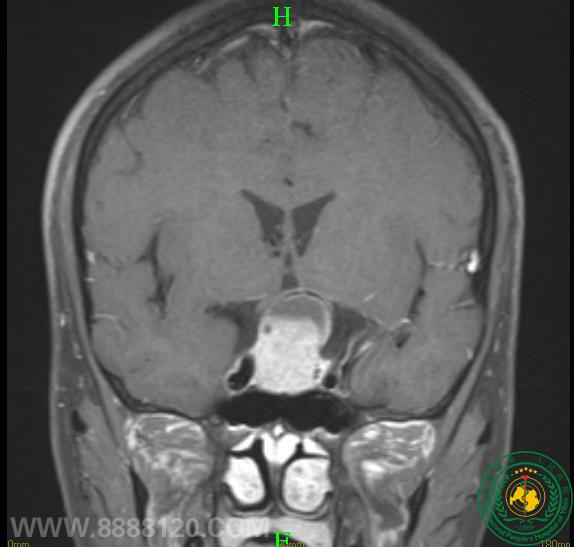

眼睛突然看不清,需警惕是颅内肿瘤作怪

眼睛突然看不清,需警惕是颅内肿瘤作怪15294